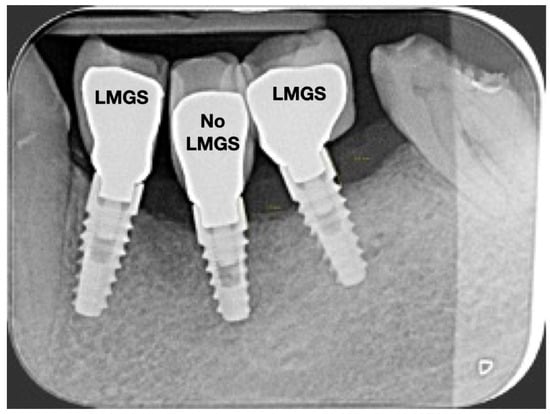

A total of 164 LMGS implants (37.4%) and 195 no-LMGS implants (42.1%) presented PIM. Differences between LMGS implants and no-LMGS implants were not statistically significant (p > 0.05). A total of 28 (6.3%) LMGS implants and 98 (21.1%) no-LMGS implants demonstrated P with a statistically significant difference (p < 0.01). Figure 2, Figure 3, Figure 4 and Figure 5 report examples of radiographs during follow-up.

Figure 5.

Radiograph of the same three (3) implants at the 15-year follow-up. Signs of P can be noted around the No-LMCS implant. (LMGS = with a laser-microgrooved collar surface; No-LMGS = without a laser-microgrooved collar surface).